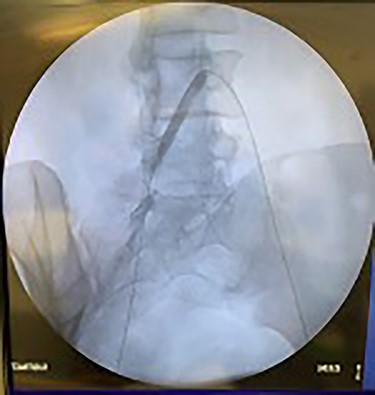

Catheter arteriogram results showed significant occlusion of the left iliac artery (Figs 3 and 4), the right iliac artery (Fig. 1), as well as the distal abdominal aorta (Fig. 2). There were numerous collateral vessels noted, indicating the presence of long-standing proximal stenosis (Fig. 1). The decision was made to use angioplasty to help widen the areas of stenosis. An 8 mm × 40 mm Passeo balloon was advanced from the right femoral artery into the left iliac artery (Fig. 7) and insufflated to 6 mmHg (Fig. 6). The balloon was allowed to remain expanded for 1 min and then was deflated. Next, the distal aorta was repaired in a similar fashion. The balloon was advanced into the distal aorta from the right femoral access and insufflated to 12 mmHg (Fig. 8). The balloon was allowed to remain expanded for 90 s.

Fluoroscopy showing dilation of the distal aorta post-angioplasty.

Fluoroscopy showing dilation of the right iliac vessel post-angioplasty.